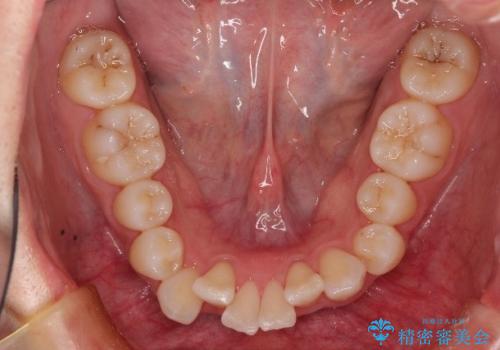

非抜歯で整える前歯の矯正

- 患者様は、前歯の重なり(叢生)が気になるとのことでご来院されました。診断の結果、奥歯を後方に移動することで前歯にスペースを確保し、非抜歯で歯列を整える方針としました。治療には審美性の高いホワイトワイヤーを使用し、奥歯の遠心移動にはリンガルアーチを装着しました。治療期間は約2年を予定し、月に一度の調整を通じて歯の動きを細かく管理しました。